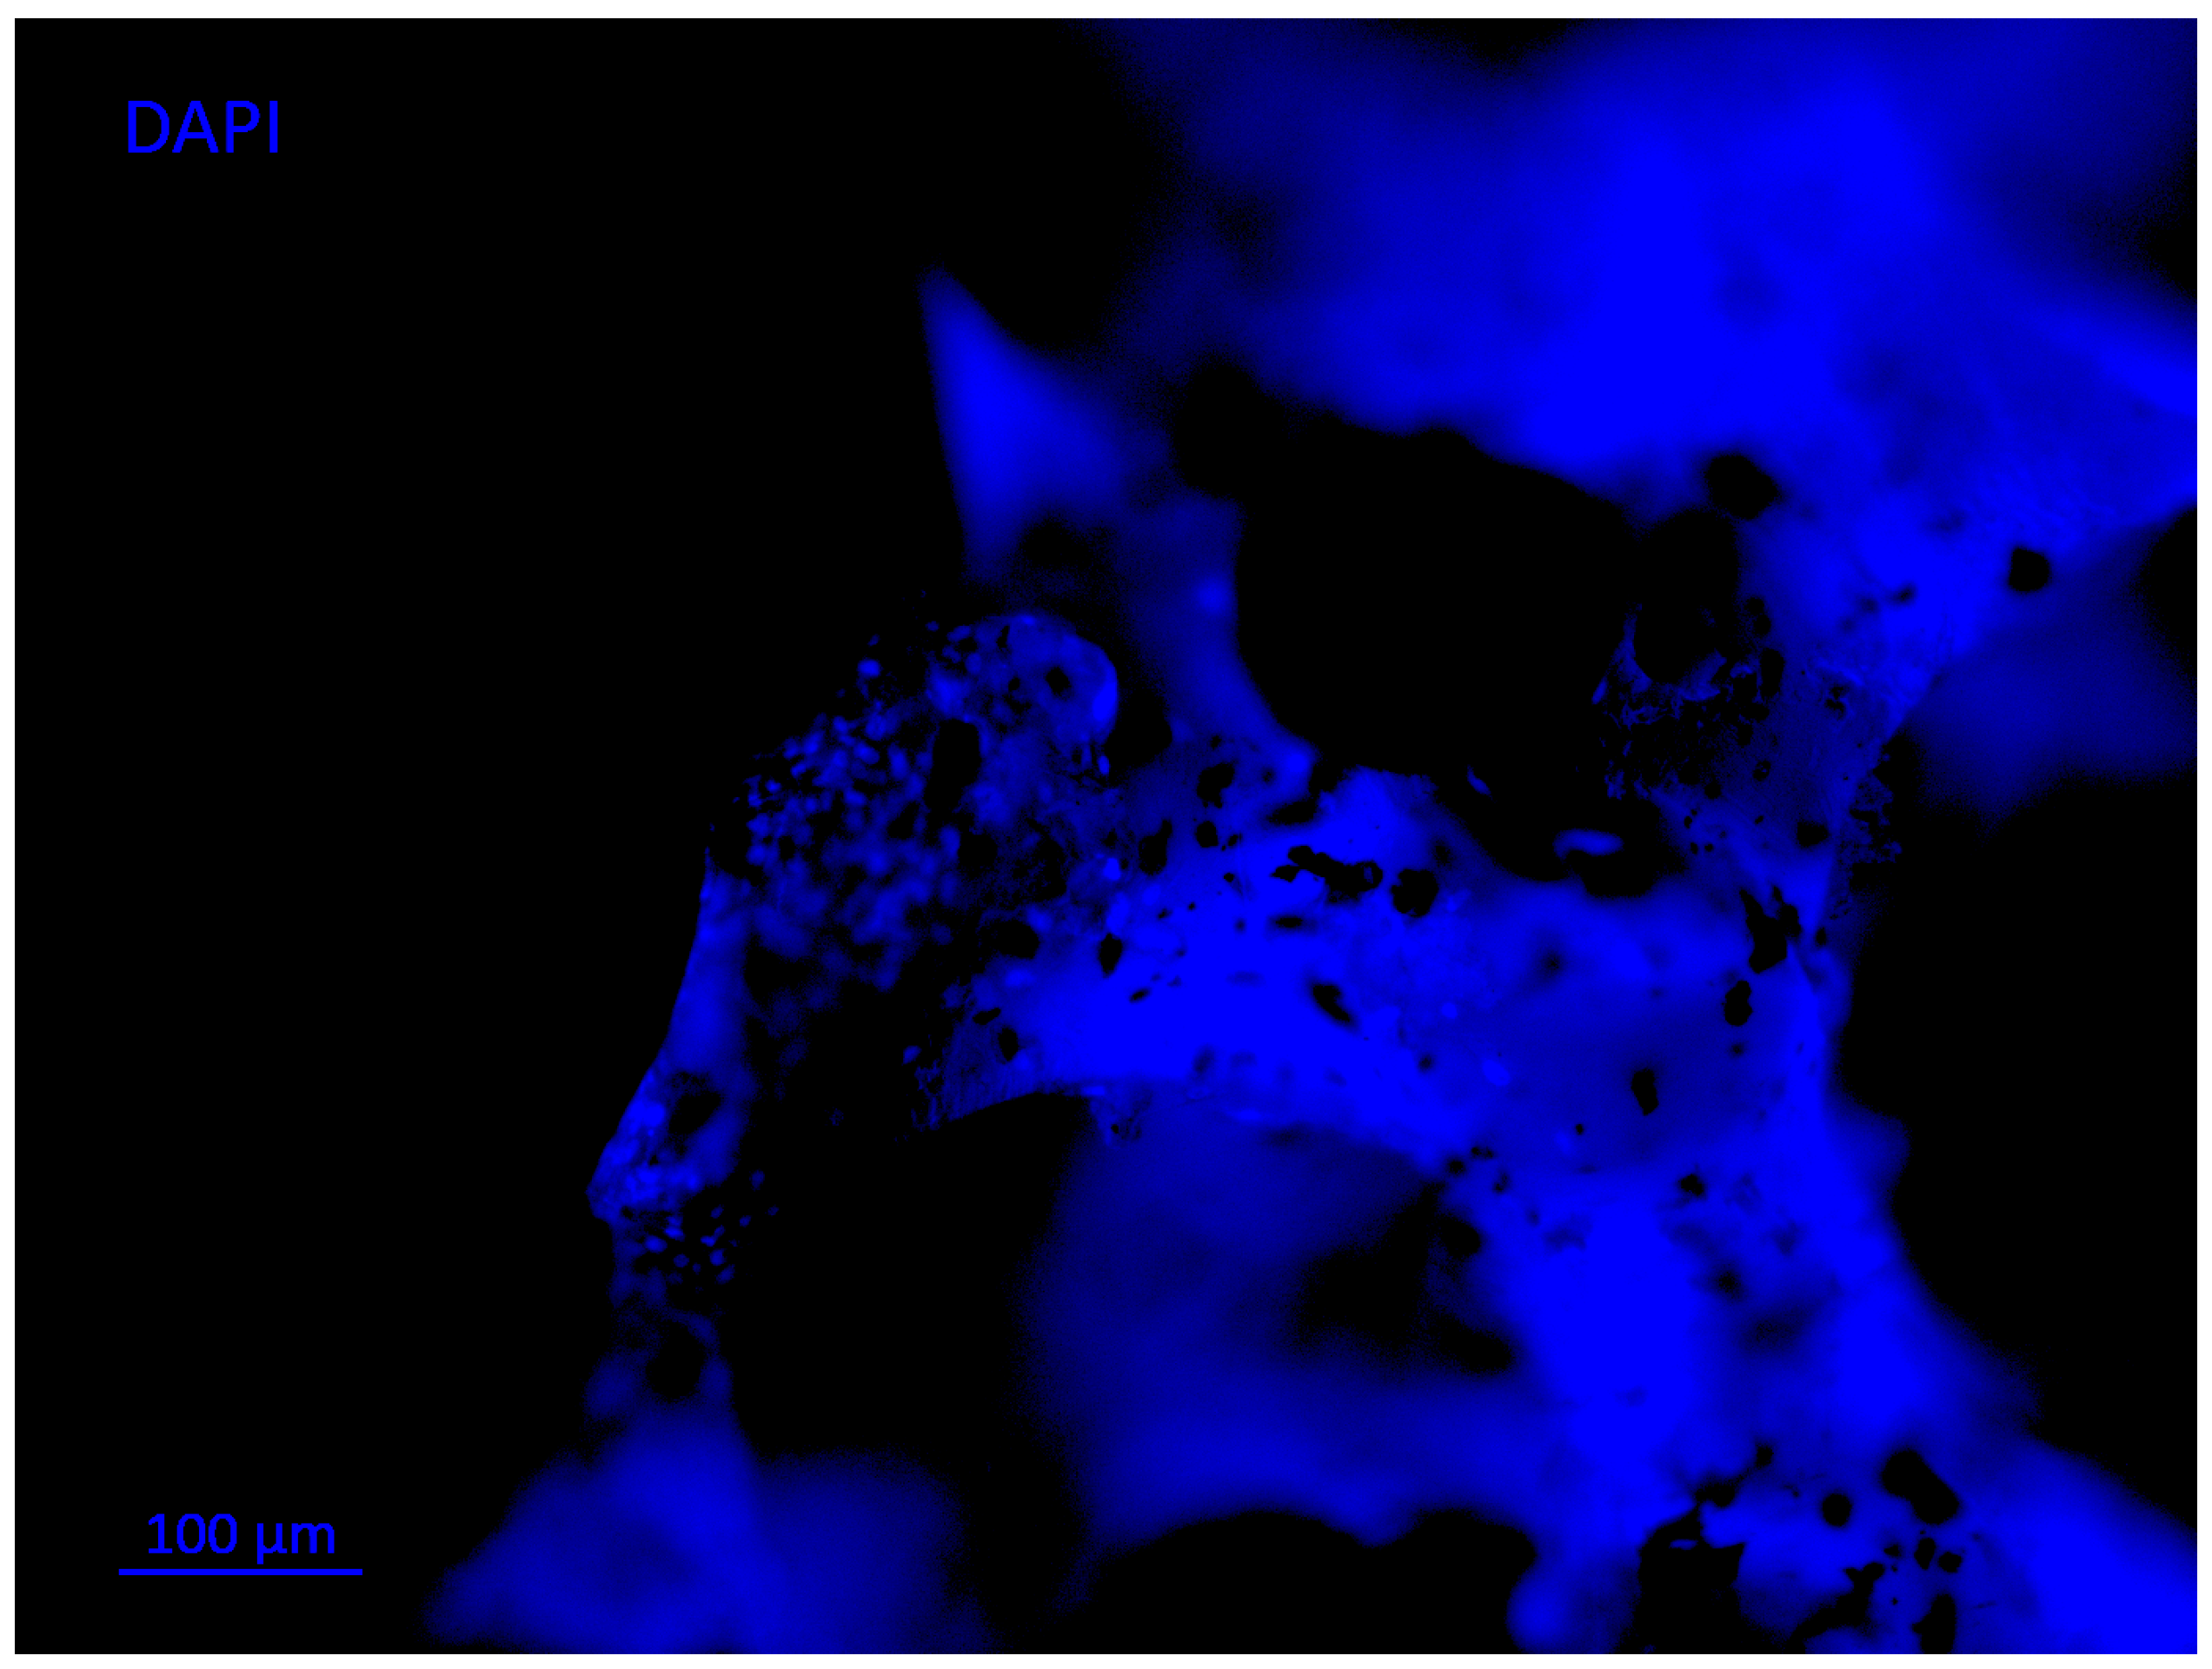

- Rosales-Ibáñez, R.; Cubo-Mateo, N.; Rodríguez-Navarrete, A.; González-González, A.M.; Villamar-Duque, T.E.; Flores-Sánchez, L.O.; Rodríguez-Lorenzo, L.M. Assessment of a PCL-3D printing-dental pulp stem cells triplet for bone engineering: An in vitro study. Polymers 2021, 13, 1154. [Google Scholar] [CrossRef]